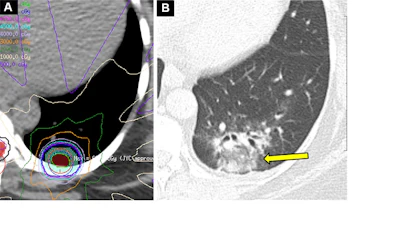

Acute radiation-induced pneumonitis after SBRT (65 Gy, four fractions) in a 53-year-old woman with leiomyosarcoma of the uterus with a left lower lobe metastasis manifesting as a small nodule (not shown). (A) Axial dosimetric reconstruction of a CT image obtained for SBRT planning shows the metastasis receiving the maximal isodose (6500 cGy). (B) Axial CT image obtained 12 months after completion of RT shows focal ground-glass and consolidative opacities confined to the treatment plan (arrow). Note that acute lung injury with SBRT typically manifests later than with conventional RT (i.e., >12 weeks after completion of therapy), and in 25% of patients, the first CT manifestations occur more than one year after completion of RT.RadioGraphics